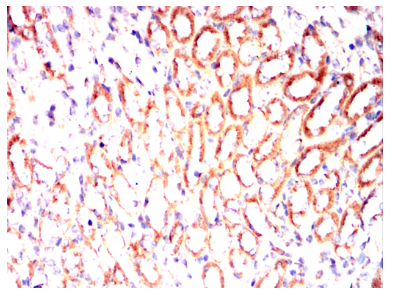

ALPL Mouse Monoclonal antibody[2F4D11]

IHC    1/200 - 1/1000